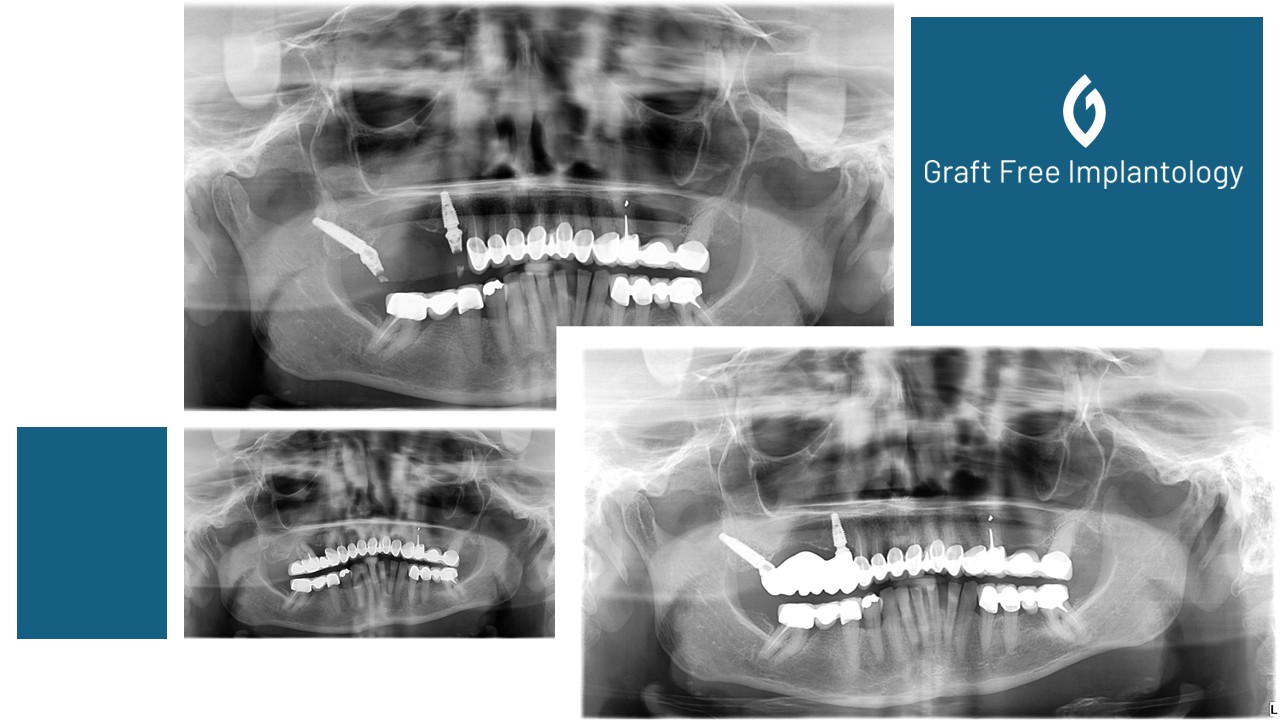

Low sinus floor indicates the need for pterygoid implant in a posterior dental bridge

To avoid sinus floor, pterygoid implants can be used quickly and safely and even accommodate immediate loading.